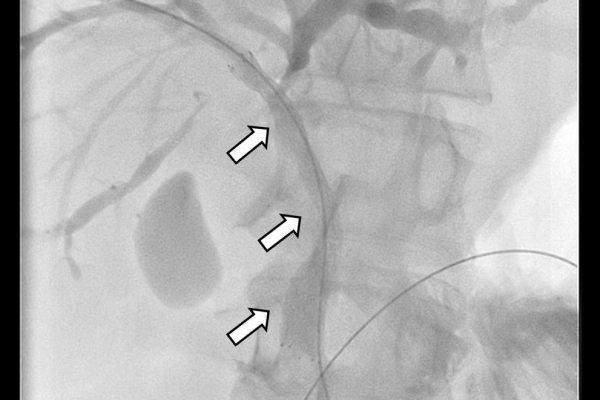

Σε πολλές περιπτώσεις πρωτοπαθών ή δευτεροπαθών όγκων ήπατος - παγκρέατος προκαλείται απόφραξη των χολαγγείων με συνοδό αποφρακτικό ίκτερο.Ο ασθενής με αποφρακτικό ίκτερο δεν μπορεί να υποβληθεί σε χημειοθεραπεία, αν δεν αποκατασταθεί ο ίκτερος με παροχέτευση των χοληφόρων.

Η παροχέτευση των χοληφόρων σε αυτές τις περιπτώσεις θα πρέπει να γίνεται άμεσα, είτε ταυτόχρονα προς τα έξω και προς το 12κτυλο (έσω-έξω παροχέτευση), είτε μόνο προς τα έξω με τη βοήθεια pigtailκαθετήρα (εξωτερική παροχέτευση)

Σε περιπτώσεις όπου υπάρχει απόφραξη των χοληφόρων και ενδείκνυται η τοποθέτηση ενδοπρόθεσης (stent), τότε η βατότητα των χολαγγείων και η αντιμετώπιση του αποφρακτικού ικτέρου μπορεί να διασφαλιστεί με την τοποθέτηση ενδοπροθέσεων (stents).